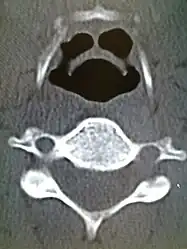

CT imaging showing the "halloween sign" -

CT imaging, is rarely needed and can have a negative effect via respiratory distress.[13]